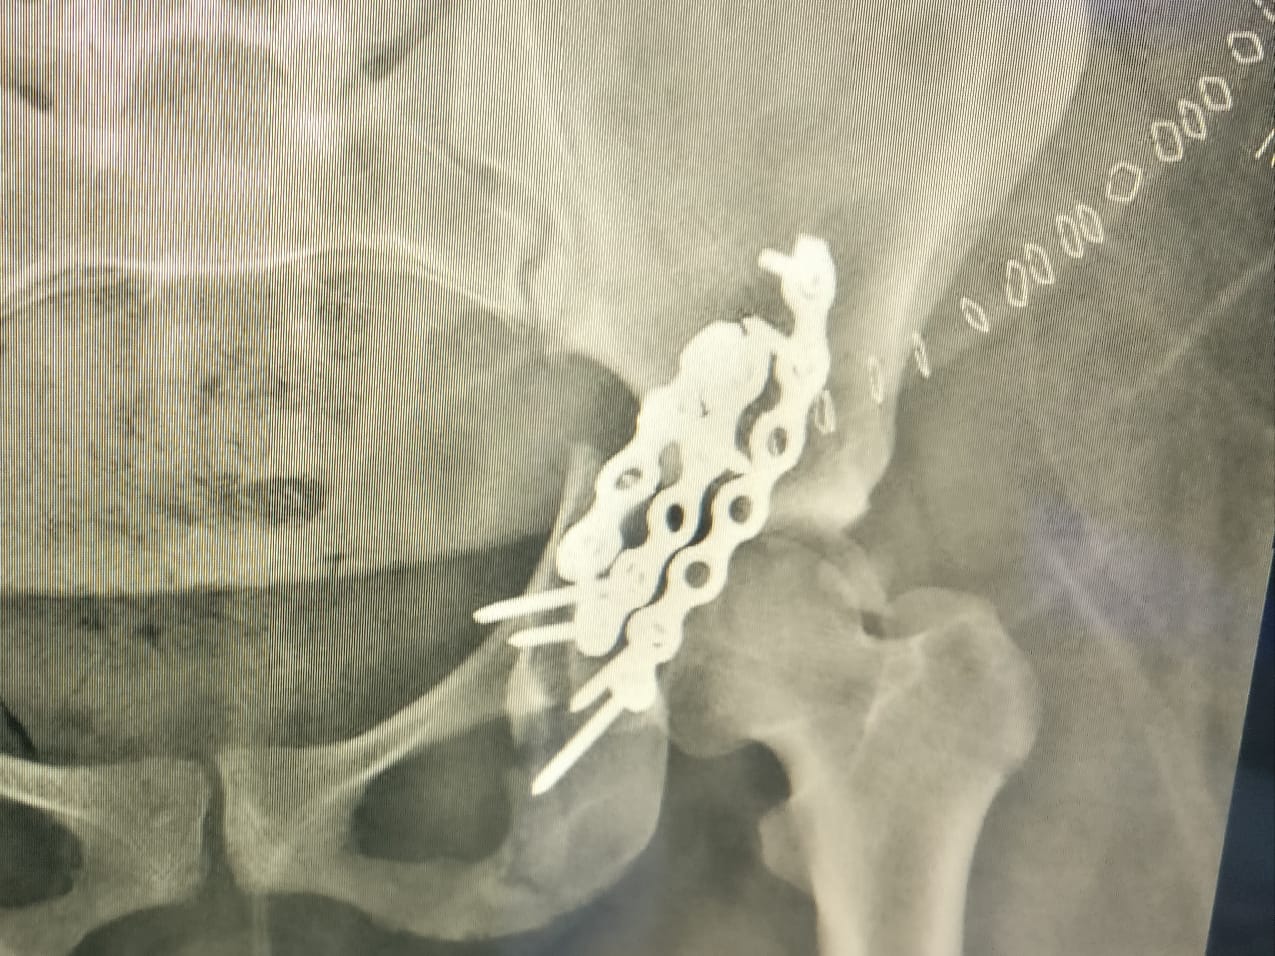

واصلت مدينة الملك سعود الطبية ممثلة بجراحات العظام وكسور الحوض، نجاحاتها في العمليات النادرة والمعقدة، حيث أنقذت أربعينية من إعاقة بالحركة جراء حادث مروري؛ نتيجة إصابتها  بخلع في فخذها الأيسر مع كسور مضاعفة في الحوض.

وأوضحت المدينة على لسان استشاري جراحة العظام وكسور الحوض والمشرف على الحالة د.حسين اليوسف، أن الحالة المعقدة كانت قد حولت لمدينة الملك سعود الطبية، بعد أن أجريت لها عملية جراحية قبل فترة لإرجاع كسور الورك، إلا أنها لم تتكلل بالنجاح.

وأشار د.اليوسف إلى أن الصعوبات في هذا النوع من العمليات تكمن في عدة أمور تتمثل في أن منطقة الحوض محاطة بأهم وأكبر الأوعية الدموية والأعصاب التي قد تؤدي إصابتها بحياة المريض أو تشل من حركته، بالإضافة إلى خطورة الالتهابات تزداد في حالات المراجعة والتي تجرى فيها العملية بعد عمليات سابقة في نفس المنطقة، كما أن الدراسات أثبتت تضائل نسبة النجاح في حال تأخر العملية أو إعادتها خصوصا عندما تكون الإصابة شديدة و نسبة التفتت عالية كذلك فإن التليفات الناجمة عن جروح عمليات الولادة تجعل الوصول إلى الكسر أمرا ليس بالسهل.

ونوه د.اليوسف بأن أنه بعد استقبال الحالة، تم إجراء تدخل جراحي على مرحلتين، حيث كانت الأولى عبارة عن إزالة الشرائح والتفتتات  من المفصل في الخلف ليقوم بعدها بإرجاع الكسر وترميم المفصل وتثبيته ليعود بعدها في المرحلة الثانية لتكرار العملية للجزء الأمامي من الكسر.

وأفاد د.اليوسف بأن العملية تكللت بالنجاح وحالة المريضة جيدة بعد إعادة الكسر وترميم المفصل ، وخضوعها للعلاج الطبيعي والتأهيل وهي الآن في طريقها للحركة الطبيعية بإذن الله.

تجدر الإشارة إلى أن عمليات جراحة الحوض والورك من العمليات المعقدة في جراحة العظام، وتُعد مدينة الملك سعود الطبية رائدة في هذا المجال بما تمتلكه من كفاءات مؤهلة ومتخصصة، وأصبحت مرجعاً هاماً يستقبل العدد الأكبر من هذه الإصابات من جميع أنحاء المملكة.